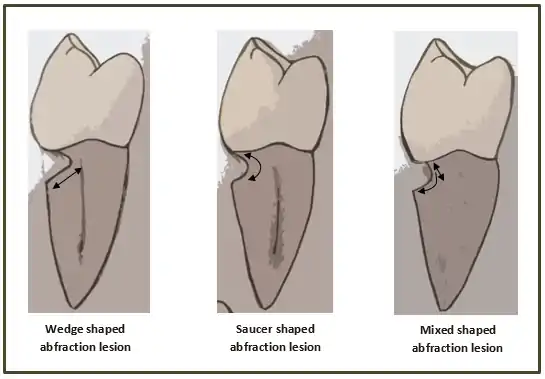

When looking at abfraction lesions there are generally three shapes in which they appear, appearing as either wedge, saucer or mixed patterns.[6] Wedge and saucer shaped lesions are the most common, whereas mixed lesions are less frequently identified in the oral cavity.[6] In reference to figure 1, wedge shaped lesions have the sharpest internal line angles and saucer/mixed shaped lesions are either smooth internally, or a variety.